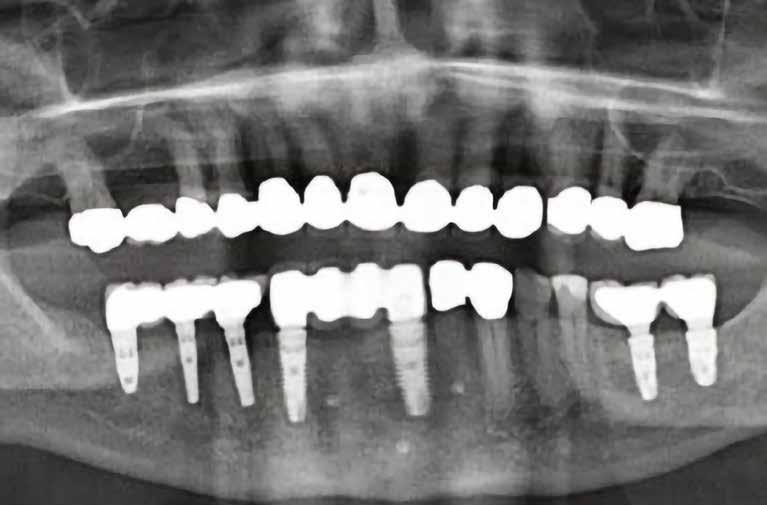

20–22. ábra: 2017-es, 2019-es és 2022-es panorámaröntgen-felvételek.

2. ábra: Dr. Park esete. 4.6-os fogon levő jelentős csontfelritkulás röntgenképe, extractio és iGBR alkalmazása Osteon Xenoval. 4 hónap múlva Dentium short implantátum, majd 4 hónap múlva korona készítése.

3. ábra: Dr. Han esete. 2.4-2.5-2.6 lokalizációban keskeny gerinc. Csontpótlás Osteon Xeno- val, majd 4 hónap múlva 3 db Dentium short implantátum behelyezése. 4 hónappal később protetikai munka.